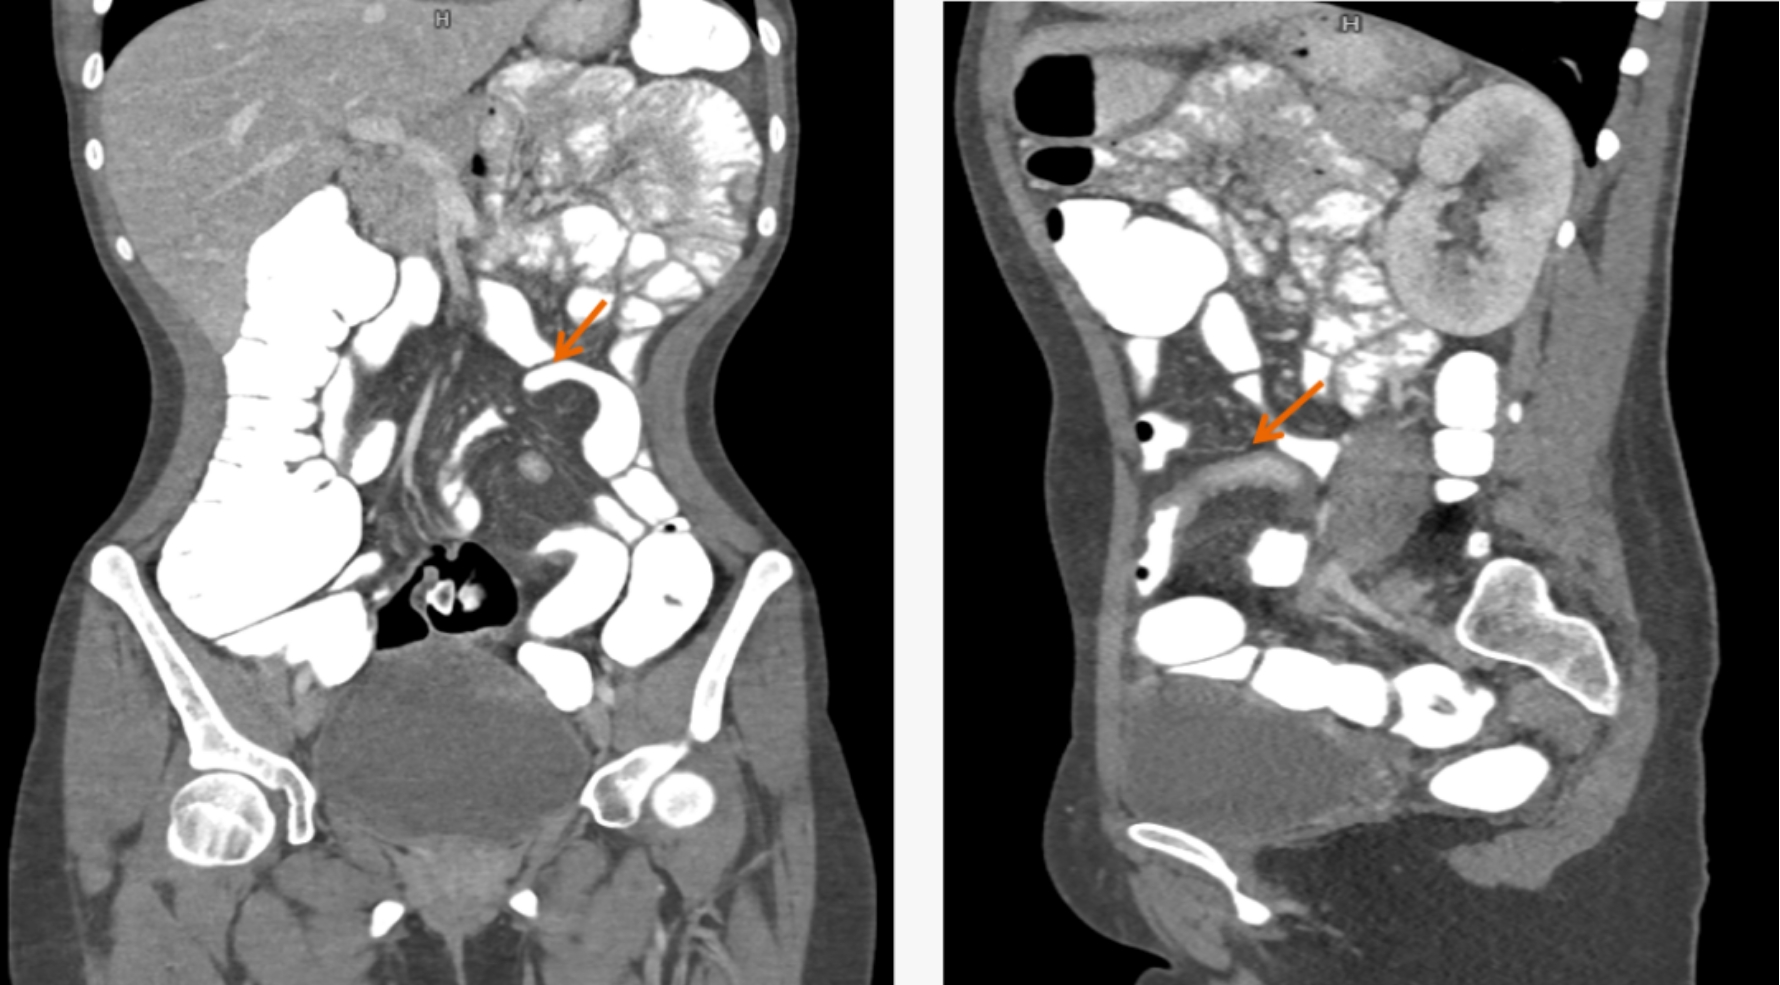

本次引進(jìn)的全新64排128層人工智能螺旋CT具有檢查更加精細(xì)、圖像更加清晰、掃描速度快和輻射劑量小等多種優(yōu)點(diǎn)。除了可進(jìn)行常規(guī)CT檢查、普通增強(qiáng)CT檢查外,還可對(duì)全身大血管、腦血管、心臟血管進(jìn)行檢查;強(qiáng)大的三維重建功能可發(fā)現(xiàn)普通DR、常規(guī)CT所難確診的病變。

用該設(shè)備做心血管系統(tǒng)檢查,能得到對(duì)比度極佳的血管圖像。大大提高了診療的精準(zhǔn)度及工作效率,有利于醫(yī)生及早發(fā)現(xiàn)微小病灶。

通過該新型CT,不僅年老體弱的病人可以接受CT冠脈造影檢查,得到的CT圖片質(zhì)量也非常清晰,對(duì)臨床診斷的價(jià)值更大。

該設(shè)備,可以在短時(shí)間完成對(duì)冠狀動(dòng)脈缺血、肺栓塞、主動(dòng)脈瘤的一站式檢查,也可在在短時(shí)間完成對(duì)頭部血管、頸部血管、腦實(shí)質(zhì)血液灌注的一站式檢查,為腦卒中和急性胸痛患者的早期診斷和治療能力贏得黃金時(shí)間。